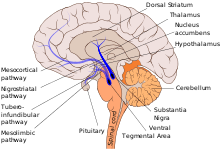

Nigrostriatal pathway

The nigrostriatal pathway or the nigrostriatal bundle (NSB), is a dopaminergic pathway that connects the substantia nigra with the dorsal striatum (i.e., the caudate nucleus and putamen). It is one of the four major dopamine pathways in the brain, and is particularly involved in the production of movement, as part of a system called the basal ganglia motor loop. Dopaminergic neurons of this pathway synapse onto GABAergic neurons.[1]

The following are considered part of the nigrostriatal pathway.

Substantia nigra

The substantia nigra is located in the midbrain. It has two distinct parts, the pars compacta and the pars reticulata. The pars compacta is part of the nigrostriatal pathway and relays information to the basal ganglia by supplying dopamine to the striatum. The pars reticulata in conjunction with the Globus pallidus in the basal ganglia allows for inhibition of the thalamus.

Dorsal striatum

The dorsal striatum is located in the subcortical region of the forebrain. It is divided by a white matter tract called the internal capsule into two parts: the putamen and the caudate nucleus. The putamen and caudate both input information from the cerebral cortex, thalamus, and substantia nigra.

The nigrostriatal pathway connects the substantia nigra with the dorsal striatum. It is one of the four major dopamine pathways in the brain, and is particularly involved in modulation of the extrapyramidal system. Dopaminergic neurons in the nigrostriatal pathway synapse onto GABAergic neurons in the basal ganglia.[1] and in part make up the basal ganglia motor loop. Along with the other dopaminergic pathways, it is also partially involved in reward and in the reinforcement of memory consolidation.[3]